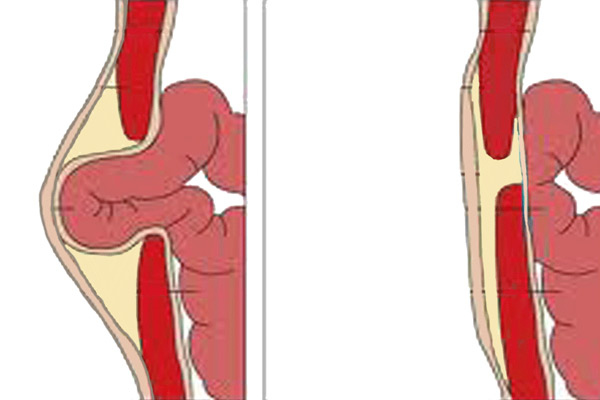

Λαπαροσκοπική Τεχνική Κήλης

Ανοιχτή Τεχνική Κήλης